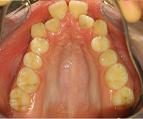

Con frecuencia ocurre que algunos dientes no están correctamente colocados. Esto puede producirse tempranamente por problemas de espacio en las arcadas dentales, es decir, el espacio disponible en las mismas es menor que el que necesitan los dientes. Como consecuencia se produce lo que se conoce como apiñamiento. También la presencia de hábitos en la edad infantil puede tener efectos similares.

Debido a estos problemas de posición dental, el funcionamiento de los dientes y articulaciones mandibulares puede verse afectado. También puede producirse un aspecto poco estético de la dentición.